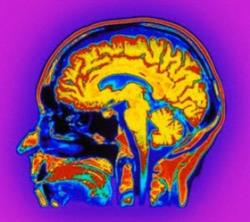

محققان دانشگاه کمبریج و واحد علوم مغز و شناختی شورای تحقیقات پزشکی در تحقیقات جدید خود به ارائه بینش عمیقتری در مورد مغز انسان پرداختهاند که بر اساس آن، عمر مغز کمتر از تصورات پیشین است.

به گزارش سرویس پژوهشی ایسنا، محققان نشان دادند که تغییرات گزارش شده قبلی در مورد سن مغز با استفاده از افامآرآی ممکن است بر اساس تغییرات عروقی و نه فعالیت نورونی باشد.

این بررسیها نشان داده که مغزهای پیرتر ممکن است بیشتر از تصورات پیشین مشابه مغزهای جوان باشند.